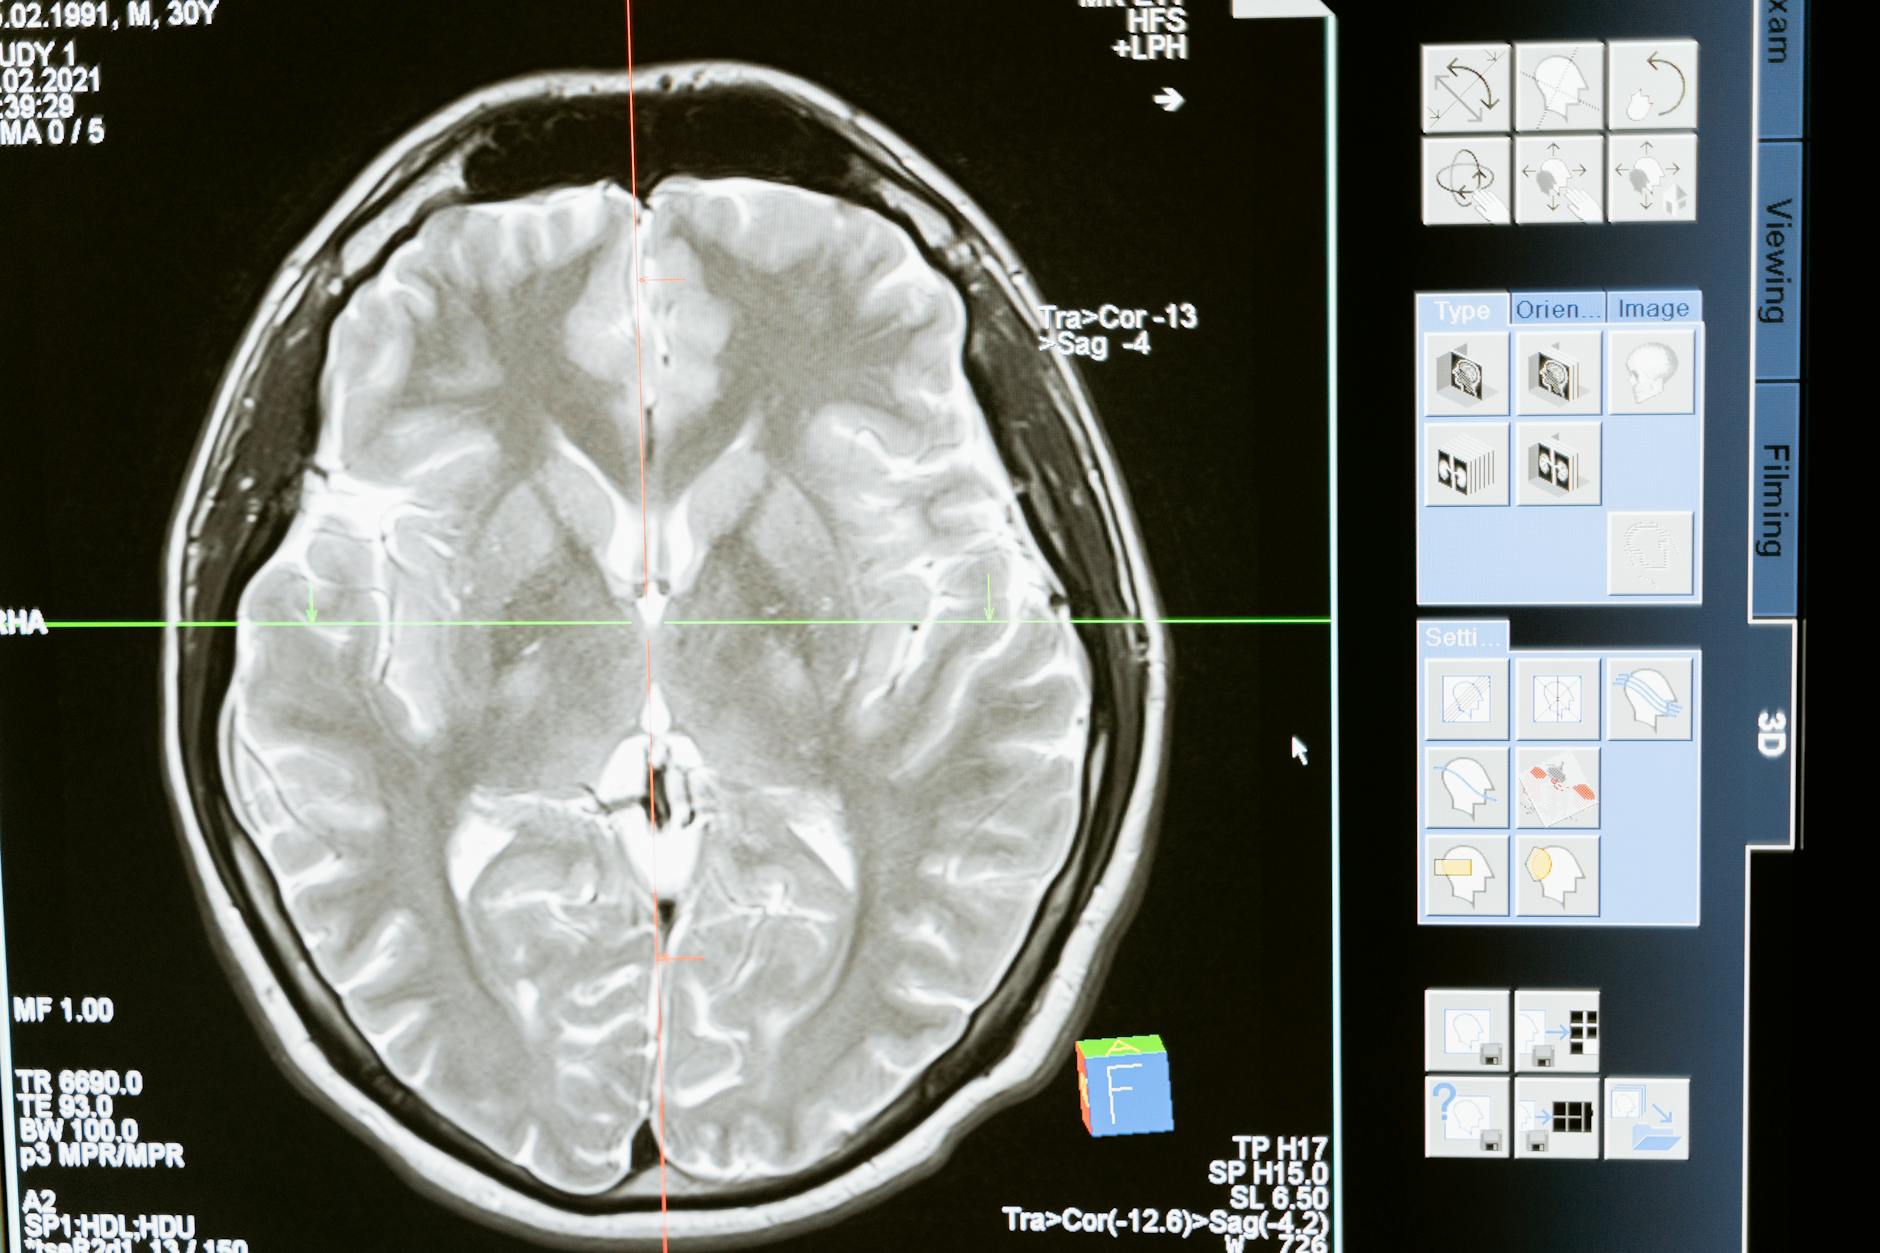

During a neurofeedback session, electroencephalography (EEG) sensors placed on the scalp detect electrical signals from underlying cortical networks. These signals are processed by proprietary software algorithms — now AI-enhanced in 2026 platforms — and translated into real-time audiovisual feedback. When your brain produces target frequencies, you hear a reward tone or see a visual cue; when it drifts outside parameters, the feedback pauses.

This feedback loop, repeated across dozens of sessions, drives lasting changes in cortical excitability and synaptic efficiency. Neuroimaging research demonstrates that neurofeedback training induces measurable changes in cortical thickness, white matter integrity, and functional connectivity between prefrontal and limbic regions. The anterior cingulate cortex — your brain’s error-detection and conflict-resolution hub — shows particular sensitivity to neurofeedback-driven remodeling.

No credible neurofeedback protocol begins without a comprehensive quantitative EEG (qEEG) brain map. This 19-channel assessment captures your resting-state brainwave patterns across all frequency bands and compares them against a normative database of age- and sex-matched individuals. The qEEG identifies your specific dysregulation signatures — whether that manifests as excess high-beta in parietal sites, alpha deficiency in occipital regions, or frontal theta excess consistent with chronic fatigue. Your protocol is built entirely from this individualized data, not from generic templates.